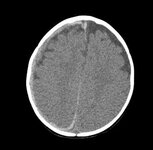

CT findings in fatal abusive head trauma often reveal significant brain oedema with loss of grey-white differentiation and effacement of the ventricles. Subdural blood is often difficult to appreciate in such cases

From the personal collection of Alice Newton, MD; used with permission